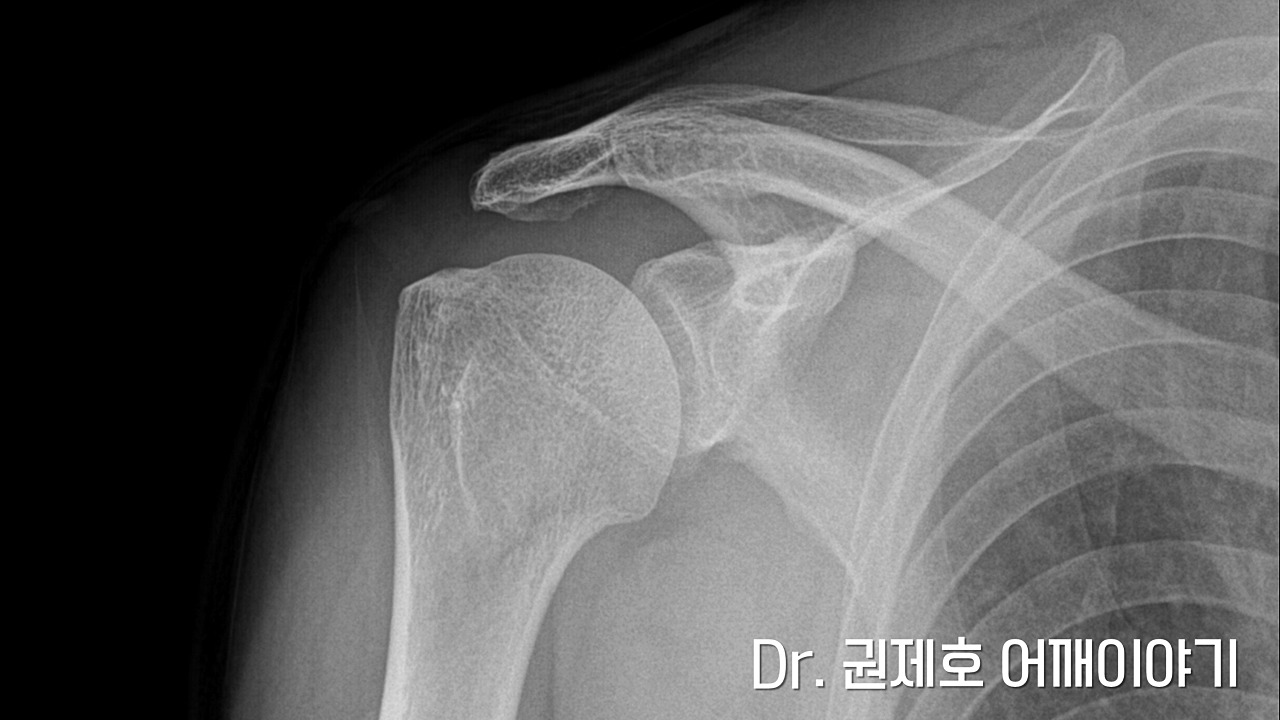

진료를 보신 분은 아시겠지만 가장 기본적인 검사는 방사선 사진입니다. 검사에서 보면 견봉이라는 뼈 끝에 뼈가 자라난 것이 보입니다. 저렇게 원래의 뼈가 아닌 세월의 흔적으로 자라난 뼈를 골극이라고 표현한다. 간혹 뼈가 다친 것이 아닌데 왜 검사를 하느냐 하시는 분들이 있다. 뼈가 다치지 않아도 이러한 변형이 나타나기 때문에 본다고 생각하면 될 것 같습니다.